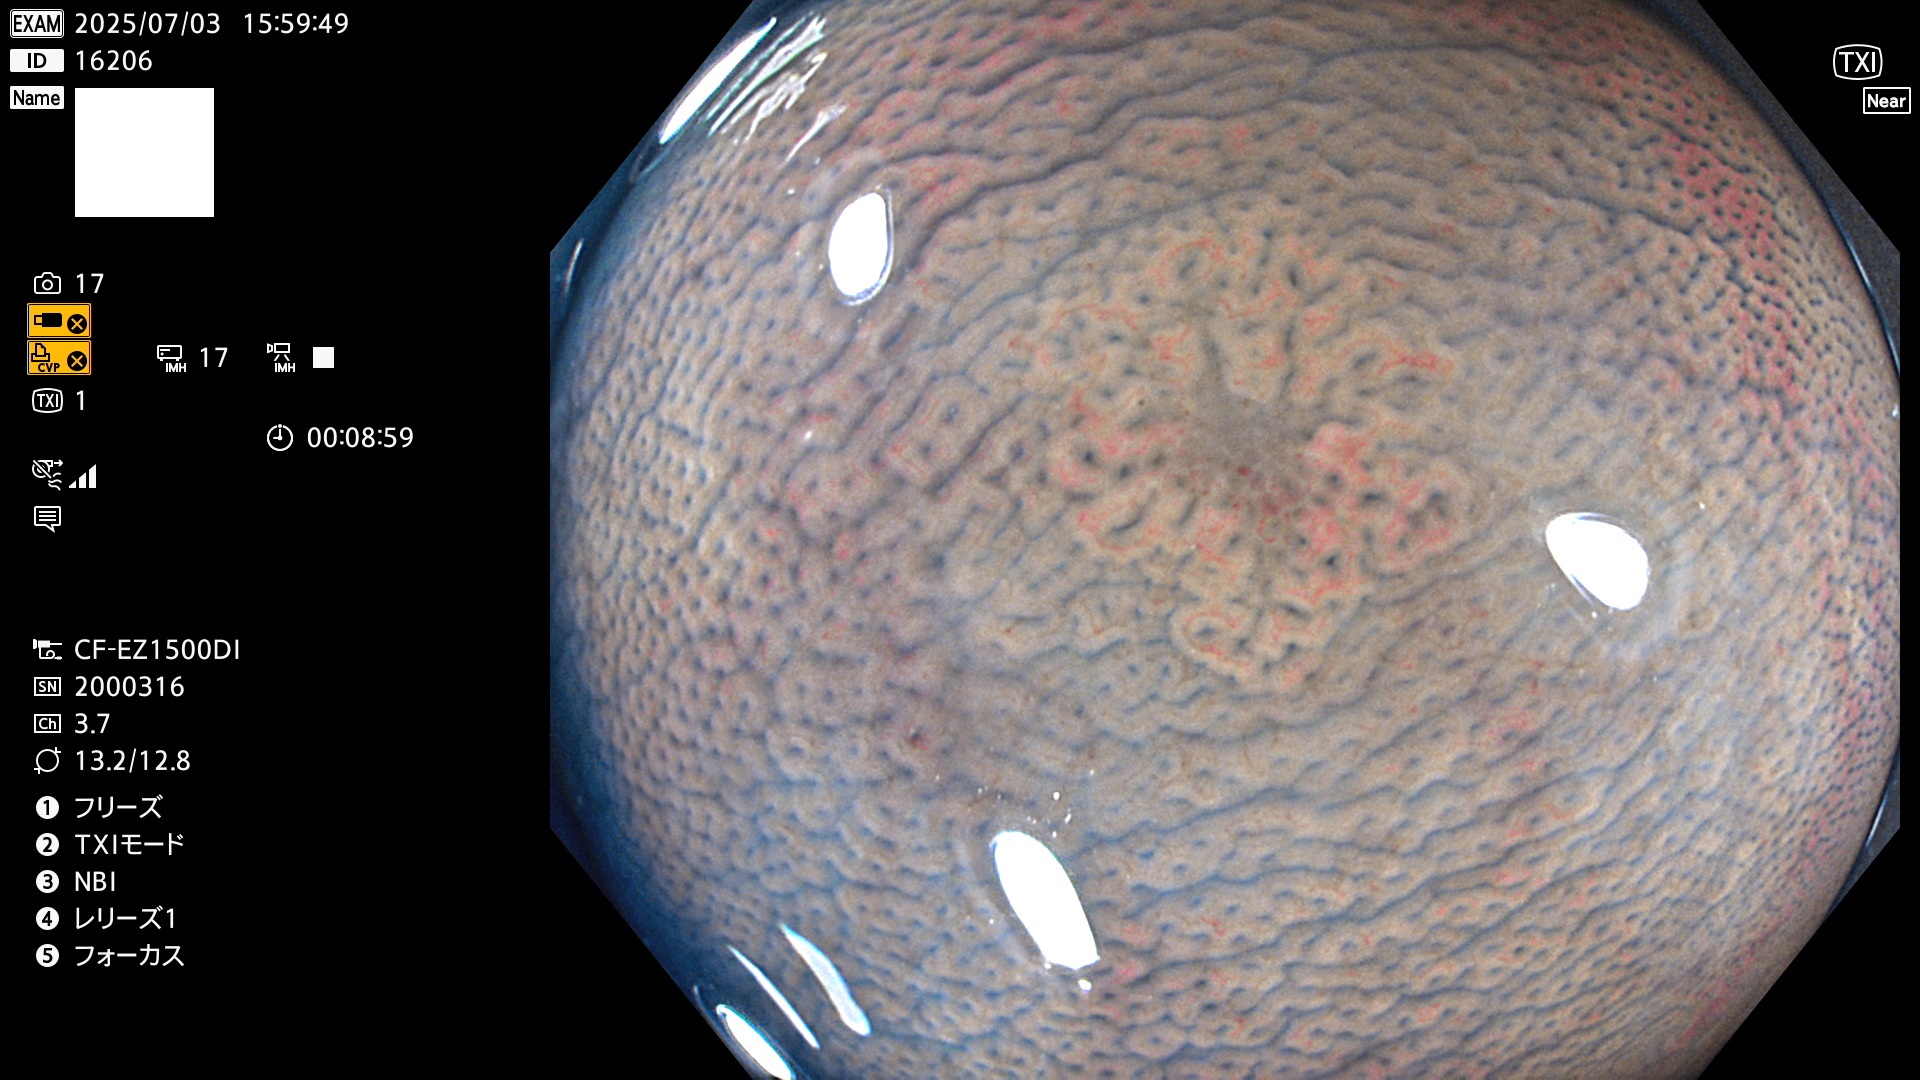

2025年7月3日〜7月6日の4日間(40件)8個 (Uc_ADR=8/40=20%)

完全に平坦な物をUb、陥凹している物をUcと呼びます。Ubは認識が困難で、Ucはびらん(炎症)と紛らわしいために見落とされやすく、「内視鏡後・大腸癌」の原因になります。